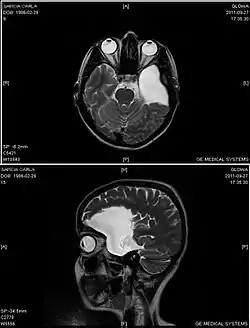

الكيسات العنكبوتية (بالإنجليزية: Arachnoid cysts) هي عبارة عن سائل دماغي شوكي مغطى بالخلايا العنكبوتية والكولاجين[1] والذي قد ينمو بين سطح الدماغ وقاعدة الجمجمة أو على الغشاء العنكبوتي، وهو أحد الطبقات السحائية الثلاث التي تغطي الدماغ والحبل الشوكي.[2] وتُعد الكيسات العنكبوتية الأولية هي اضطراب خلقي بينما الكيسات العنكبوتية الثانوية هي نتيجة لإصابة في الرأس أو صدمة.[3] تبدأ معظم حالات الكيسات الأولية خلال فترة الرضاعة؛ ومع ذلك قد يتأخر ظهورها حتى سن المراهقة.

![]() صورة بالرنين المغناطيسي لامراة تبلغ من العمر 25عامًا مصابة بكيسة عنكبوتية جبهية صدغية يسري. صورة بالرنين المغناطيسي لامراة تبلغ من العمر 25عامًا مصابة بكيسة عنكبوتية جبهية صدغية يسري. | |